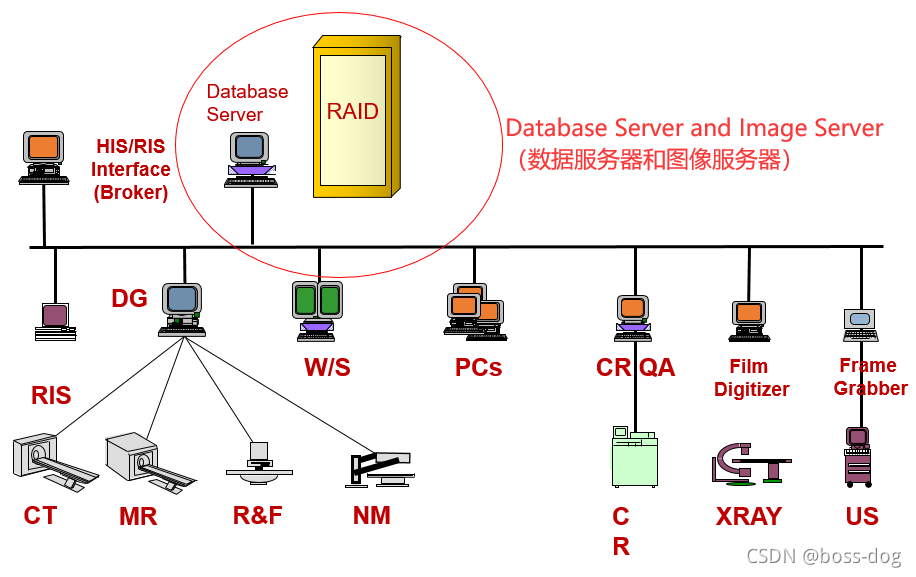

数据库服务器(PACS控制器)的作用:

1.是PACS的核心部分

2.将HIS/RIS(病人的信息)和 PACS 进行融合整合在一起

3.对于新的病人要建立文档、对病人的文档进行管理

4.管理阅读工作列表和用户配置文件

5.管理系统内的数据传输

6.支持数据挖掘和教学研究(比如对某个病人,调取其近三年内的CT图像)

图像数据库(RAID)的作用:

1.支持在线(快速存取)图像、文件的存储和分发装置(比如做急诊的话,需要将CT图像尽快交给医生去做判断)

2.支持同步图片、文件的输入和输出转移操作

3.最多可以保存三个月的图片、文件,超过三个月的可以通过光盘等存储

4.拥有可衡量的数据处理能力